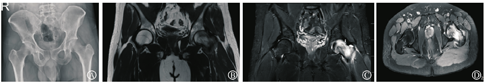

患者男,31岁,2018年5月10日出现不明原因左髋疼痛,左腹股沟、大腿前方钝痛,跛行,抗痛性步态,活动负重时加重,休息后减轻,到外院就诊,查双侧髋关节MRI,提示左股骨头内占位病变,遂行左股骨头穿刺,病理检查见:组织间隙增宽,血管周围水肿。病理报告:骨小梁及黄骨髓组织,骨小梁结构稍紊乱,未见坏死骨细胞(图1)。予非甾体消炎药(塞来昔布)治疗。治疗1周后,患者症状改善不明显,于2018年5月17日来上海中医药大学附属岳阳中西医结合医院,骨伤科门诊就诊,诉腹股沟、大腿前方钝痛,刺痛为主,痛处不移。查体:腹股沟压痛明显,左髋关节活动受限,抗痛性步态。双侧髋关节正位片未见明显异常。双侧髋关节MRI示左侧髋关节腔内见少量液体信号影;左侧股骨头、颈及粗隆间可见片状T1WI低信号,T2抑脂高信号影、边界不清,提示左侧股骨头颈部骨髓水肿(图2)。行各项血液相关检查,包括血常规、肝功能、血脂、肾功能、肿瘤指标;自身免疫指标包括补体C3、补体C4、免疫球蛋白A、免疫球蛋白G、免疫球蛋白M、类风湿因子、抗核抗体(antinuclear antibody,ANA)、双链DNA抗体(抗ds-DNA)、可提取核抗原(extractable nuclear antigen,ENA)多肽抗体谱、系统性红斑狼疮特异性(anti-Stephanie Smith, Sm)抗体、抗U1小核糖核蛋白抗体(u1 anti-small nuclear riboneoprotein, SnRNP)、系统性硬皮病特异性抗体(anti-sclerosis1-70, Sc1-70)、抗Jo-1抗体、着丝点、抗髓过氧化物酶抗体、抗蛋白酶3抗体、抗肾小球基底膜抗体、抗环瓜氨酸肽抗体(anti-cyclic citrullinated peptide antibody)、抗心磷脂抗体IgG、抗心磷脂抗体IgA、抗心磷脂抗体IgM、人类白细胞抗原(human leukocyte antigen,HLA)-B27均正常、血沉26 mm/h。上述检查中除血沉轻度升高外,其余指标均无异常。结合影像、病史、体征、病理检查、血液化验结果,可以排除感染、自身免疫性疾病、创伤、股骨头坏死或者肿瘤等原因引起的髋部疼痛,初步诊断为BMES。